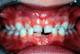

Offener Biss infolge fortgesetzten Lutschens. Infolge des Lutschens können die Zähne nicht richtig herauswachsen und finden keinen Kontakt zueinander. Das Lutschen sollte jetzt aufhören.